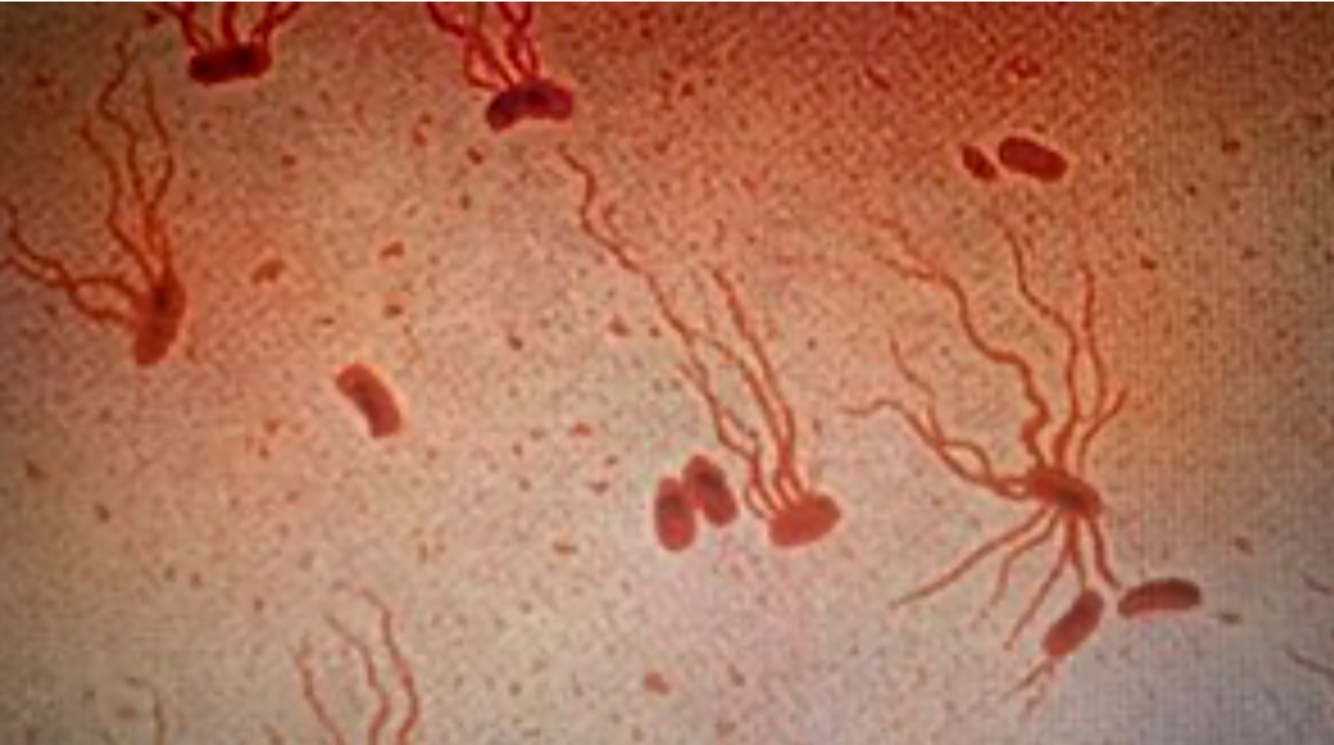

Salmonella typhi Characteristics

Enteric Bacilli

• Rod Shaped (bacillus)

• Flagella (Motile)